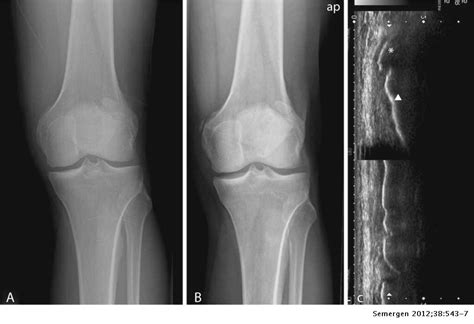

Good result after surgical treatment of Pellegrini-Stieda ...

Good result after surgical treatment of Pellegrini-Stieda ... from media.springernature.com